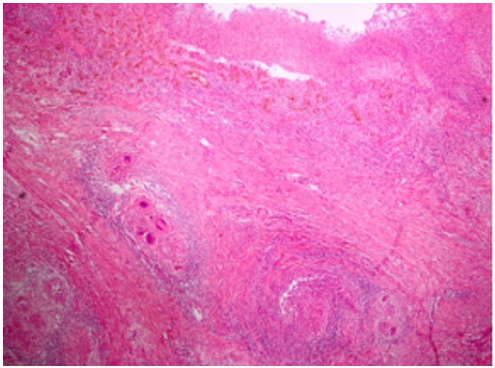

The expected findings on histopathological examination include often classified granulomas surrounding the ulcers and particularly located in the submucosa showing tendency to coalesce in intestinal tuberculosis, and discrete ulcers, deep fissuring ulcers and noncaseified granulomas in CD. Although more commonly occurring in patients with UC, sometimes regeneration polyps can be seen around the ulcer sites macroscopically in patients with CD (Figures 4 & 5) [12]. In conclusion, the treatment must be tailored according to the localisation, severity and complications of disease in patients diagnosed with IBD based on clinical and histopathological findings. Depending on the localization of the disease, drugs targeting certain regions of the gastrointestinal tract may be used, or systemic corticosteroids and immunomodulatory drugs can be preferred. Surgical therapy must be preferred if the therapies fail to achieve remission or if the patients develop complications such as obstruction/fistula, remain refractory to therapy or in the presence of neoplastic lesions in patients with IBD exhibiting disease exacerbation.

Figure 5: In the patient with intestinal tuberculosis, colonic mucosal ulcers, granulomas accompanied by caseating necrosis in the submucosa and Langhans giant cells (H&E × 40).